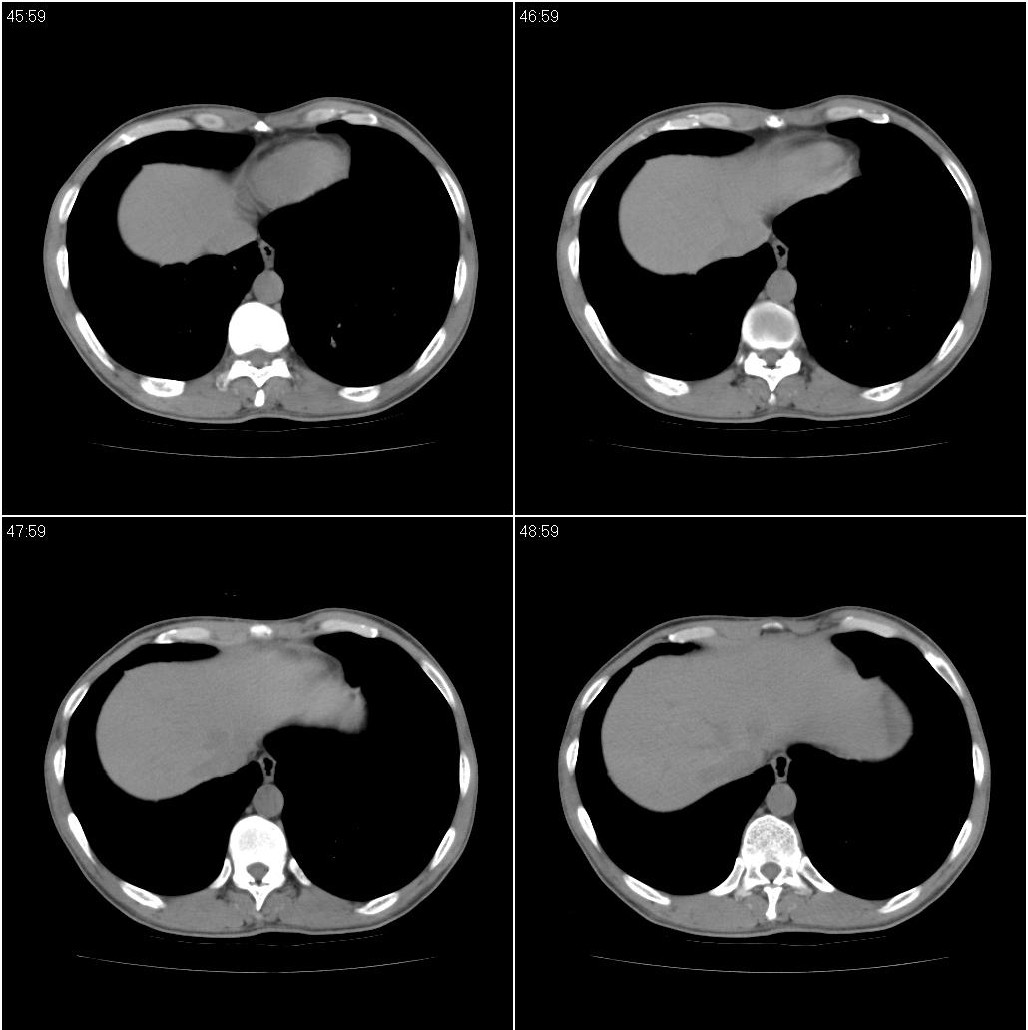

标题: CT23980:男性,47岁。近来咳痰、咳血,血沉增快(40左右),

男性,47岁。近来咳痰、咳血,血沉增快(40左右),痰中未检出结核杆菌。

两肺继发性肺结核并多发性结核球形成,部分病灶内空洞形成。

符合继发性结核表现部分空洞形成并播散